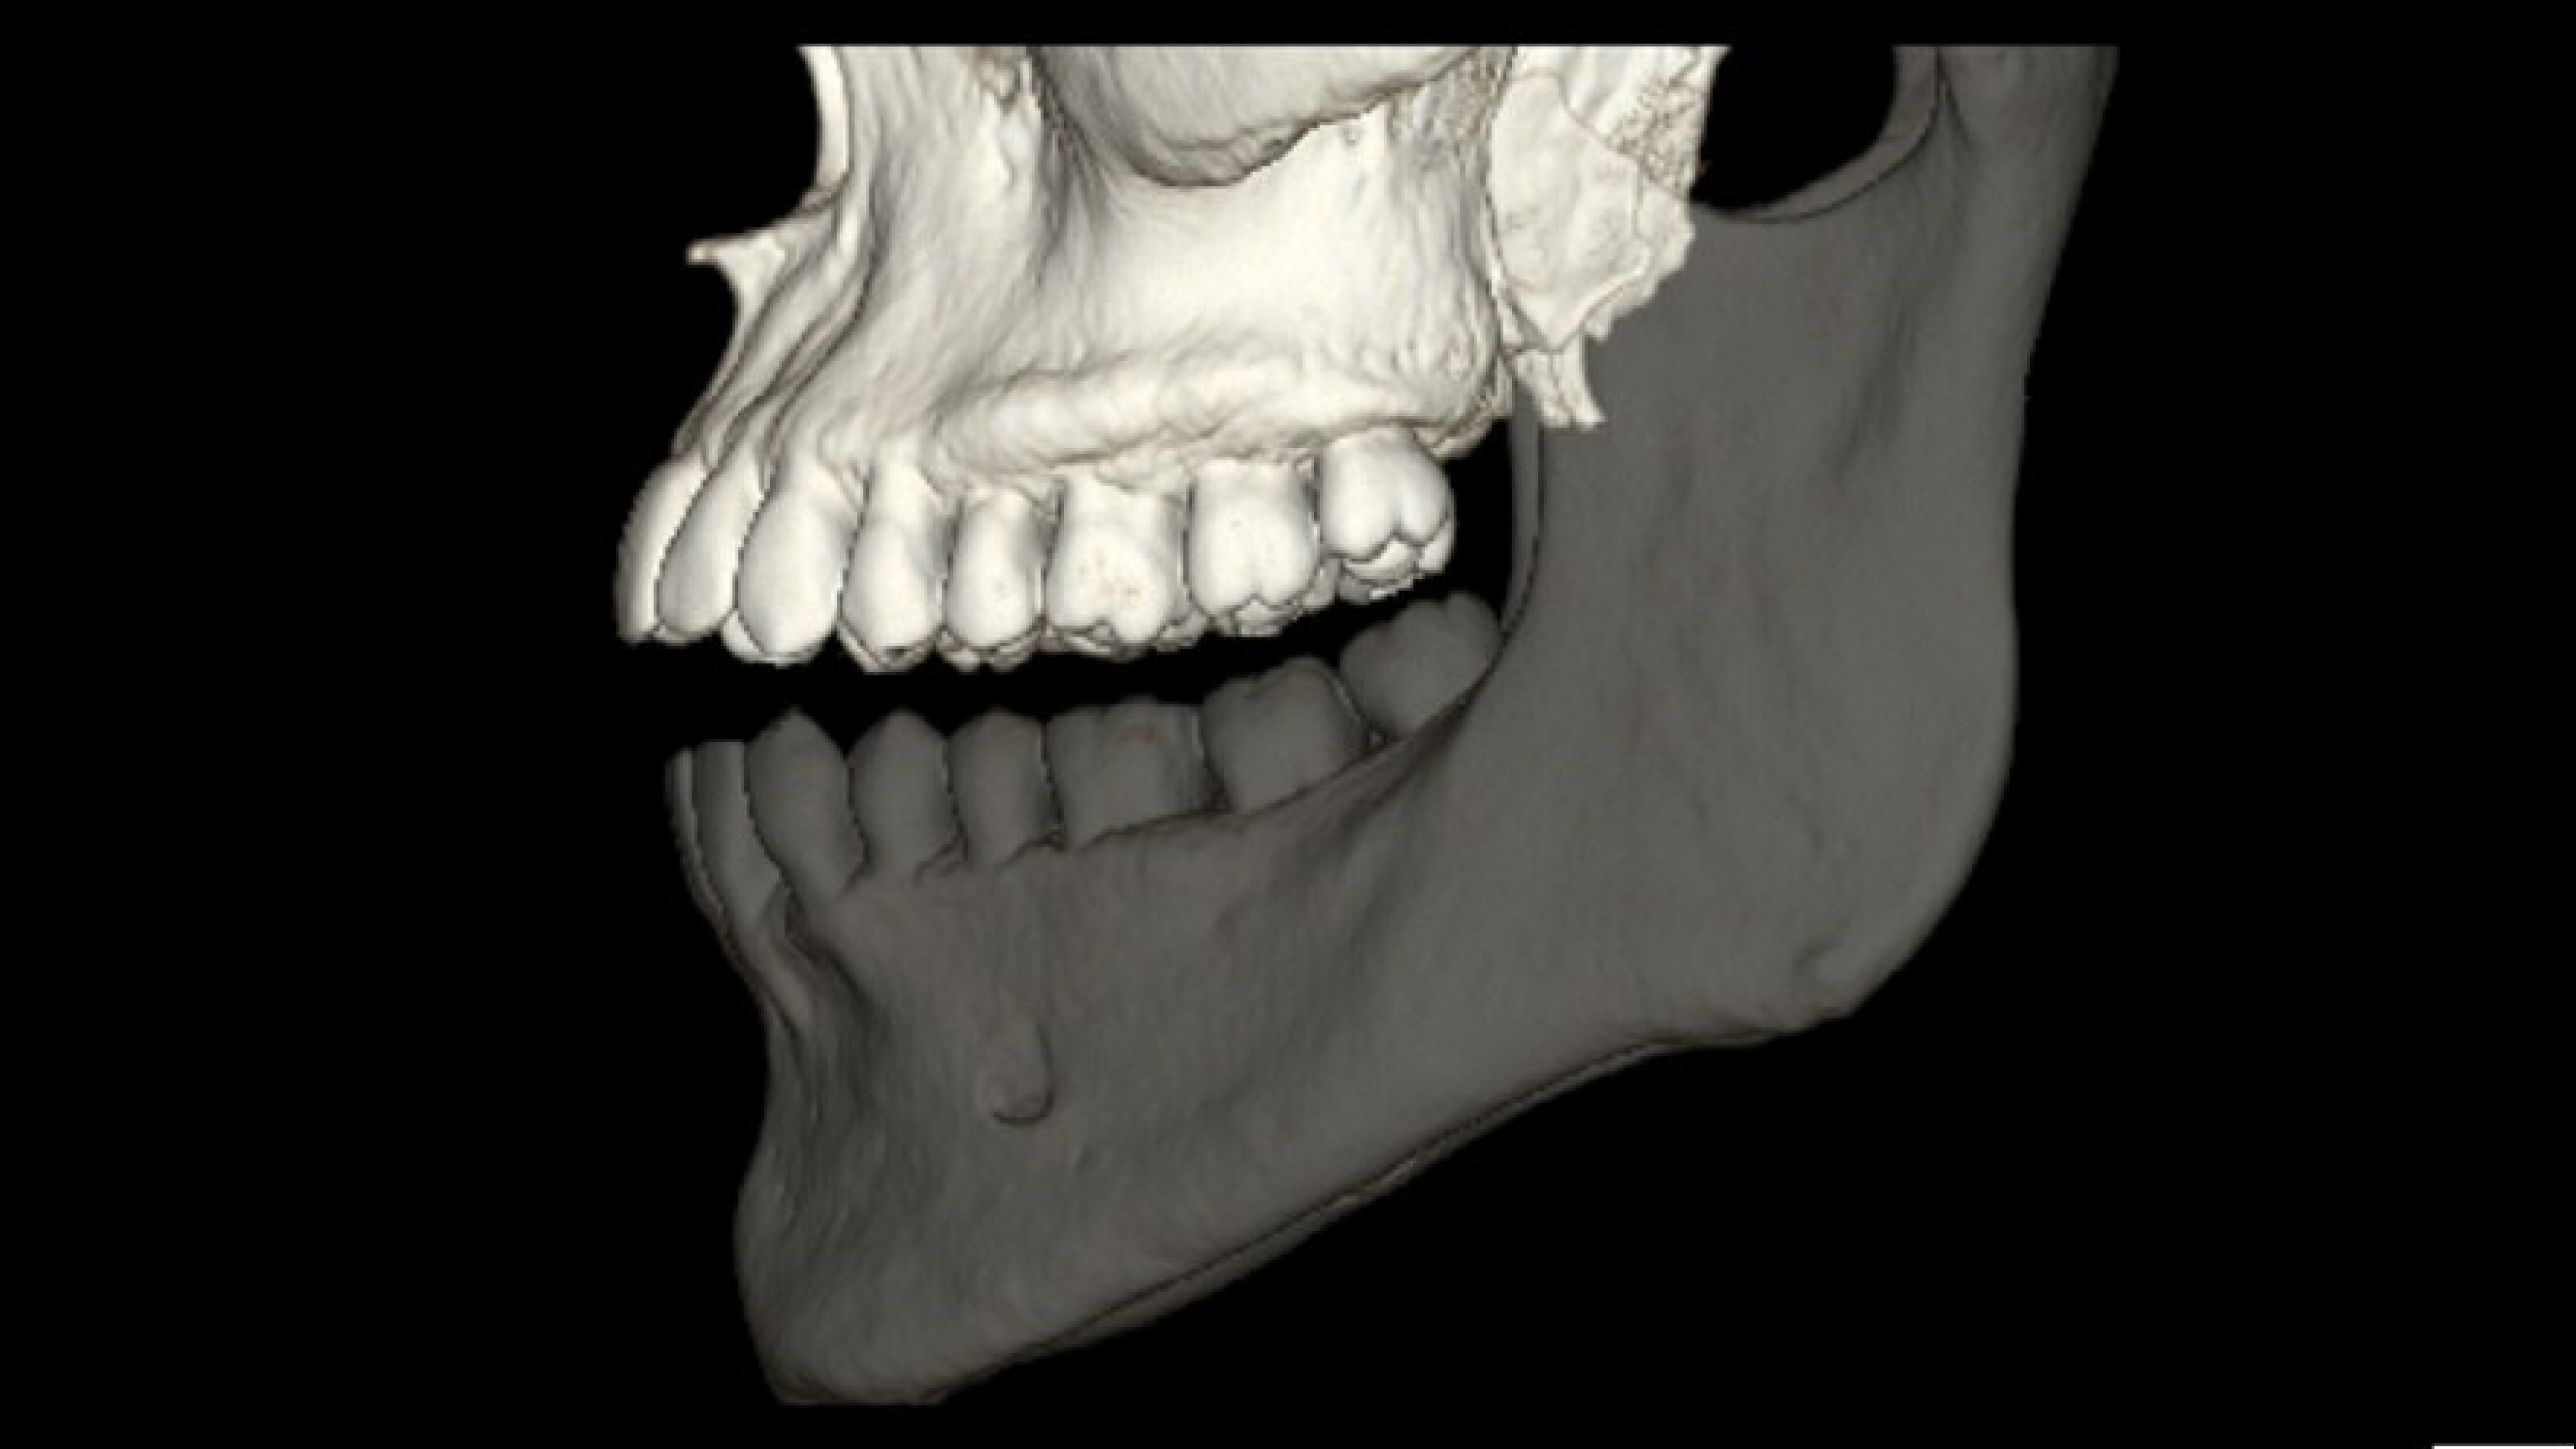

DentaScan

Real-time Oblique and Panorex reformations specific to CT dental imaging.

Panorex and oblique views

• The curve used to generate panorex and oblique views is drawn on selected axial views. It can be adjusted or redrawn easily at any time during Dentascan procedures.

• Axial panorex and oblique views remain cross referenced on the screen. Oblique views are generated in real time when the cursor is moved on axial or panorex views. A similar feature exists when the cursor is moved on a panorex or oblique view.

• Gantry tilt is supported for greater flexibility in difficult cases.